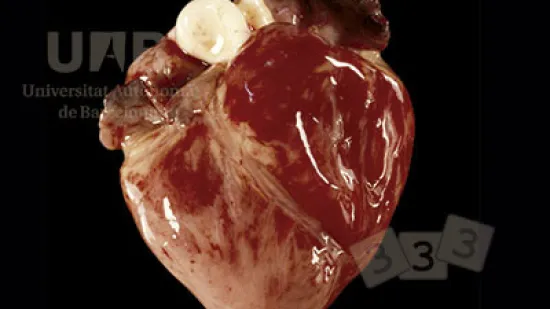

Semaine du 30-Aoû-2021

Quelle est la pathologie suggérée par cette photo ?